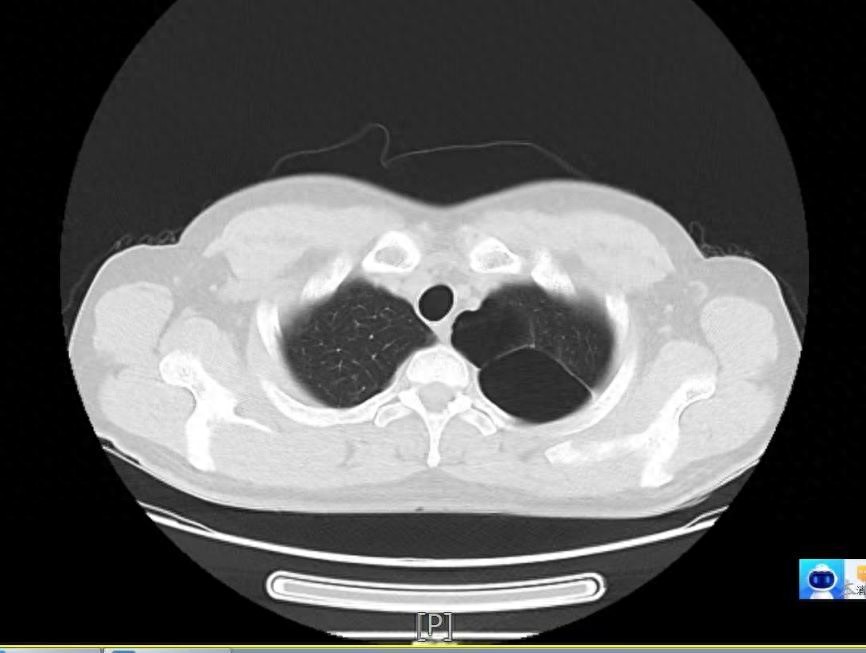

17岁的男性患者小王(化名)因反复左侧胸痛入院。胸部CT显示左肺多发肺大疱,左侧气胸。经全面检查,考虑患者气胸发作是由左肺上叶尖部明显的肺大疱破裂而引起。为避免气胸反复发作,团队决定为患者实施微创手术切除。

左肺肺大疱